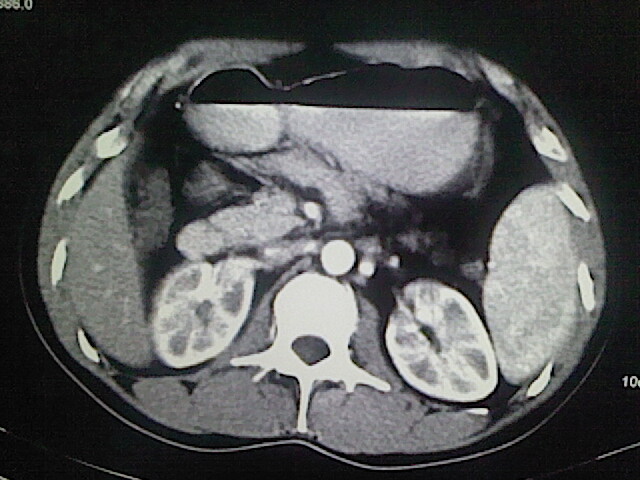

以下是引用卜一在2009-3-14 9:49:00的发言:[br]胆囊萎缩,胆囊壁不规则增厚,内部结构模糊,增强明显强化。另:肝左叶外侧段肝囊肿。支持:慢性胆囊炎!高度可疑:胆囊癌!

以下是引用余辉在2009-3-14 8:48:00的发言:[br]1)慢性胆囊炎。2)肝左叶外侧段肝囊肿。3)脂肪肝。[br]支持,胆囊萎缩,密度增高,不知b超具体有何提示,钙胆汁?结石?

以下是引用jiangjing在2009-3-14 10:18:00的发言:[br]1)慢性胆囊炎。2)肝左叶外侧段肝囊肿。3)脂肪肝。4.】建议行肝功能检查